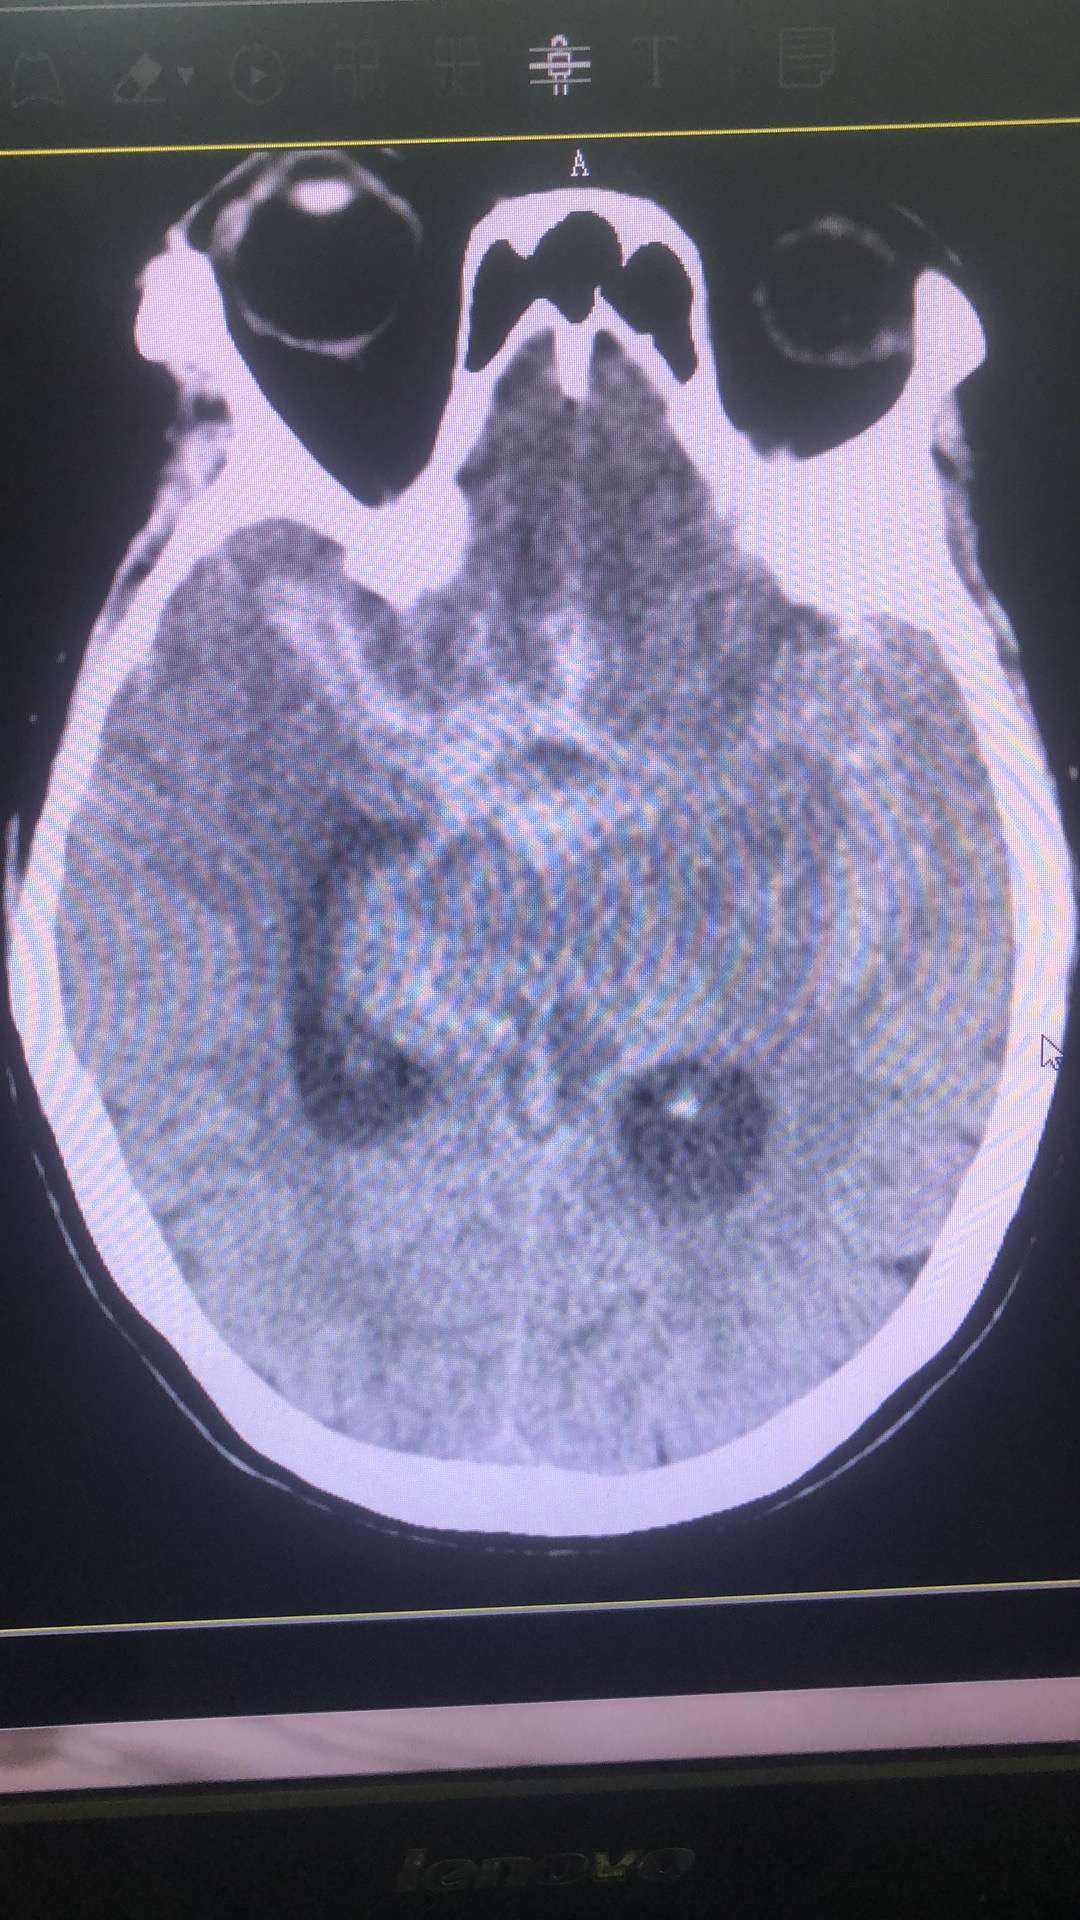

自发性蛛网膜下腔出血(SubarachnoidHemorrhage,SAH)是神经外科临床常见急症,大多数由颅内动脉瘤破裂导致,死亡率和致残率颇高。

脑血管疾病是现代人类健康面临的重要威胁 ,自发性蛛网膜下腔出血,是其中尤为危险的一类,它发病突然,即便在如今医疗水平迅速发展的条件下,死亡率和致残率仍旧很高。

近乎80%的自发性SAH 是由颅内动脉瘤破裂引起的,一旦发病需立即接受治疗 ,随着诊疗技术的提升,近年来我们对动脉瘤性蛛网膜下腔出血的诊断、手术治疗都取得了一定进展。